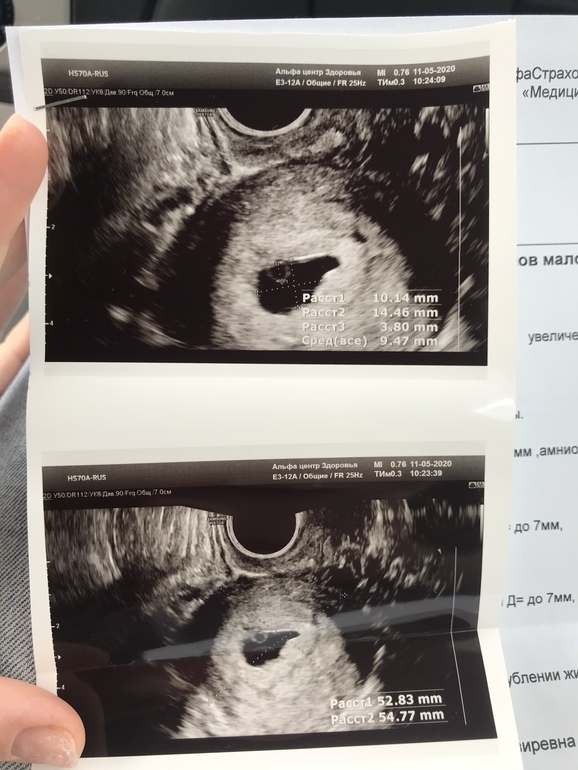

Я ходила ровно в 6 недель

Эмбриона не было ещё

Пя 10*14

Жм 3.80 так же это называется амниотическим мешком

Все хорошо будет мне вот через 10 дней сказали приходить